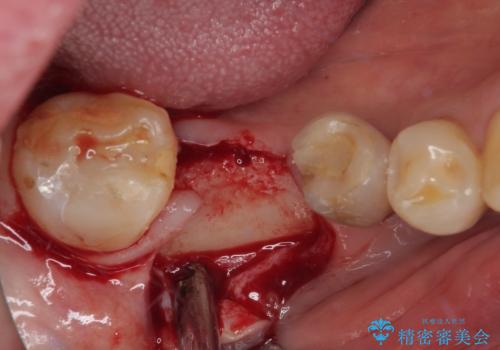

歯が割れて抜歯になってしまったとのことと、ブリッジの土台となる手前の歯は既に神経が取り除かれていて、こちらも破折するリスクが高いことから、咬合力に抵抗できるよう、インプラントによる補綴治療を行うこととしました。

インプラント埋入時に植立具合の安定性を測定したところ、十分な数値が得られたため、速やかに仮歯を装着して咬合回復をさせることができました。

外科処置を1回に抑えることができ、あっという間に治療を終えることができました。